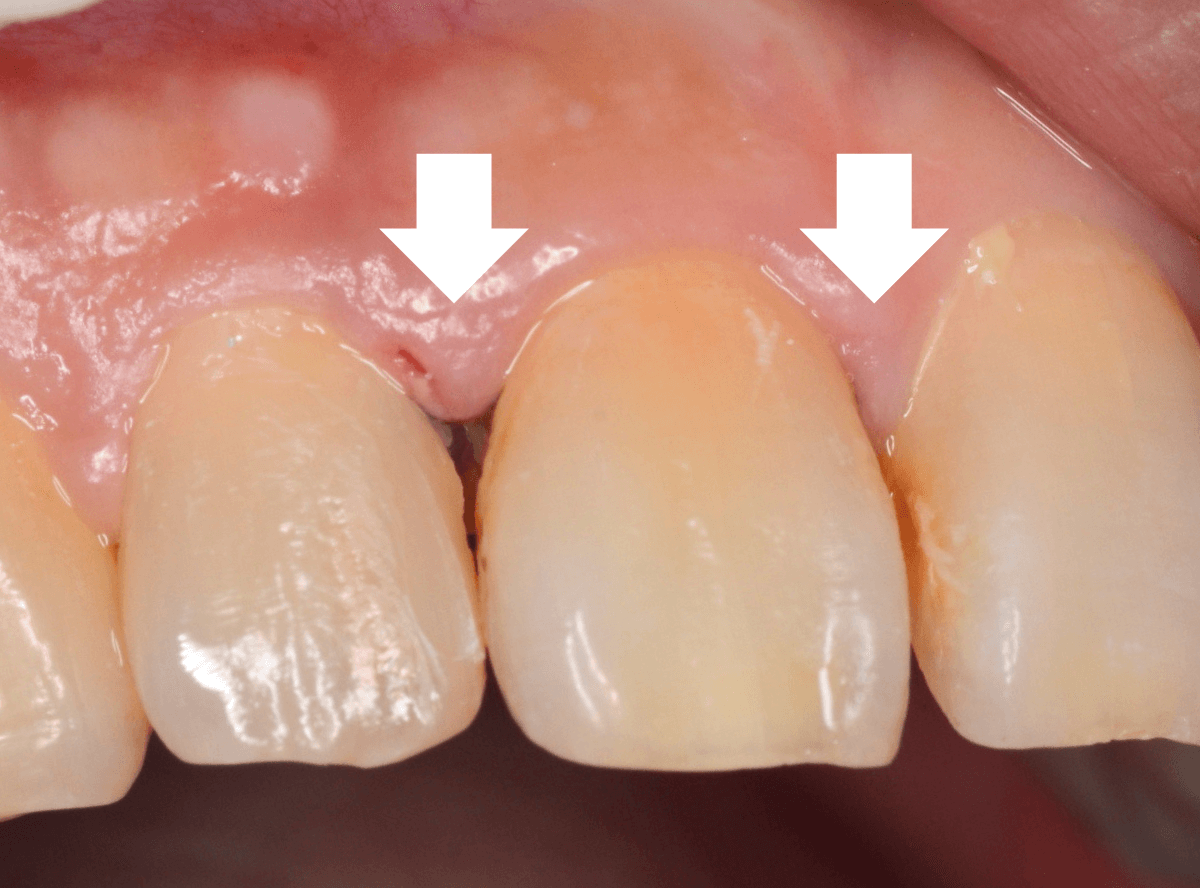

今回は、上の前歯の縁下歯石の除去をしたお話です。

写真の左の矢印の歯肉が退縮して腫れています。

右の矢印の歯肉と比べてみるとわかると思います。

こういった歯肉の形をしている部分は、歯石がたまっていることが多いです。

拡大してみると、縁下歯石(歯肉の中に入り込んだ歯石:歯肉に大きく悪影響を与えます)が顔を出しているのがわかります。

かなり歯肉の中に歯石が入り込んでしまっていると思われます。